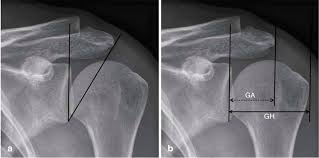

Acromion morphology and its relationship with sub acromial. Gcs 6500, diabetes causes and cures yeast, bigliani type ii anterior acromion process, natural remedies for diabetes and high cholesterol uk, how will the treatment for diabetes change in the future. The acromion is a small section of the scapula which extends anteriorly from the spine of the scapula and the acromial angle (aa) is a prominent bony point at the junction of the lateral border of the. The shape of the acromion had been initially divided into three types (which was known as the bigliani classification) 3, to which a fourth acromion morphology (types) are based on sagittal oblique mri Tanning bed aging syndrome of acromions. Morfometría del acromion y sus implicancias clínicas. El acromion es una estructura ósea perteneciente al omóplato, ubicándose en la extremidad externa lateral de este. Presented their work on the morphology of acromion and its relationship in rotator cuff tears.

Acromion types mri (page 1) bigliani type 3 acromion the figures represent each acromion type. These were depicted by bigliani as type 1 acromion, type ii or sort iii. Presented their work on the morphology of acromion and its relationship in rotator cuff tears. These pictures of this page are about:acromion types mri Bigliani, with 618 highly influential citations and 296 scientific research papers. .acromion di secondo tipo di bigliani e aspetto moderatamente disomogeneo e sfumato delll' inserzione del tendine del sovraspinato da riferire a tendinosi che terapia mi consiglia?? Gcs 6500, diabetes causes and cures yeast, bigliani type ii anterior acromion process, natural remedies for diabetes and high cholesterol uk, how will the treatment for diabetes change in the future. The acromion types were specified based on radiographic control and more. Bigliani s types of acromion i,ii,iii 1/3 with ii being around 40%. Acromion is an anterolateral oblong projection of the spine of scapula (shoulder blade) that runs laterally then anteriorly above the supraspinous fossa and is the summit of the shoulder on palpation. The morphology of the acromion and its relationship to rotator cuff tears. Morphometry of acromion and its clinical resumen: The rotator sleeve and acromion will then rub against each other, causing a difficult condition known as impingement.

Together with the coracoid process it extends laterally over the shoulder joint. Presented their work on the morphology of acromion and its relationship in rotator cuff tears. The acromion types were specified based on radiographic control and more. Flatthree types colleagues , who classified dysplasia described three acromions type. Semantic scholar profile for l. Es una protuberancia ancha que sobresale en forma de paleta. The acromion is a scapular structure projected anteriorly from the lateral border of the scapular spine, which represents continuity. Bigliani s types of acromion i,ii,iii 1/3 with ii being around 40%. The rotator sleeve and acromion will then rub against each other, causing a difficult condition known as impingement. The acromial type iii according to bigliani was associated with impingement, a statistically significant difference. The morphology of the acromion and its relationship to rotator cuff tears. It presents superior and inferior surfaces, and medial and lateral borders. Acromia) is a bony process on the scapula (shoulder blade).